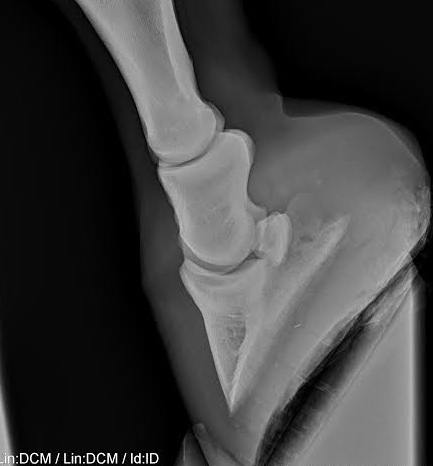

Op de eerste en derde foto kun je heel goed zien dat het hoefbeen niet meer parallel loopt aan de hoefwand. Kijk maar eens naar het puntje van het hoefbeen.

Heb hier nog wel een voorbeeldje van mijn Friese dame, in 2006 rondom bevangen geraakt. Als je goed kijkt staan er lijntjes op de hoef getekend. Zij had slechts een kleine afwijking aan het hoefbeen.

Hier een foto van een normale hoef. Dan kan je het verschil goed zien :)

Als je goed naar deze foto en de foto's van Nuvel kijkt, zie je dat bij beide foto's de hoefwand parallel aan het hoefbeen loopt (dat hoort ook!)

Dit is een zeer ernstige hoefkanteling..Het lijkt me niet rieel dit paard weer op de rit te krijgen..